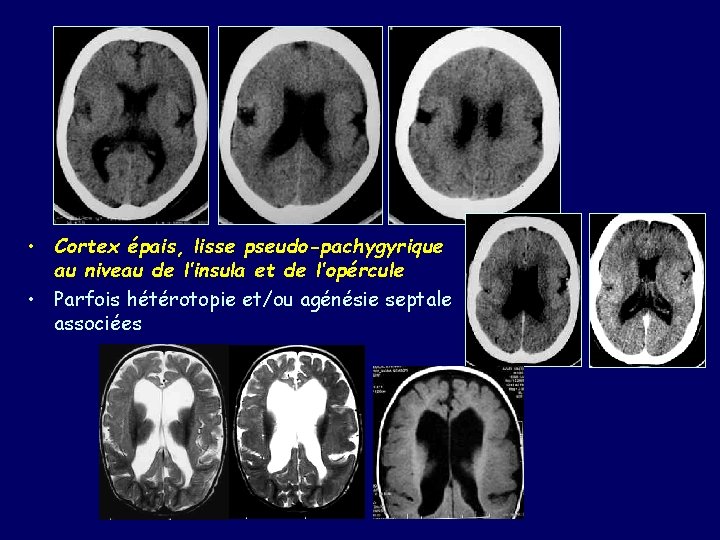

Malformations II à une organisation anormale du cortex • Polymicrogyries – – Neurones arrivés au cortex mais se plaçant de façon anormale Typiquement existe un excès de plissement Histologie : désorganisation des 6 couches Sévérité du tableau clinique, fonction de l’étendue de l’atteinte : focale, multifocale ou diffuse – uni ou bilatérale – symétrique ou asymétrique. – Localisation la plus commune : vallées sylviennes – IRM: Circonvolutions petites et nombreuses , en apparence fusionnées : aspect pseudo-pachygyrique – Intérêt des acquisitions volumiques

MALFORMATION OPERCULAIRES • Développement anormal de la scissure de sylvius et de l’opercule fronto-pariétal • IRM : identification aisée de cette entité – Insula exposée – Scissure large, verticale – Sillon central large et trop postérieur – Cortex – dysplasique, poly-microgyrique # aspect du cerveau fœtal à 20 – 24 semaines (défaut de phénomène d’opérculisation)

• Cortex épais, lisse pseudo-pachygyrique au niveau de l’insula et de l’opércule • Parfois hétérotopie et/ou agénésie septale associées